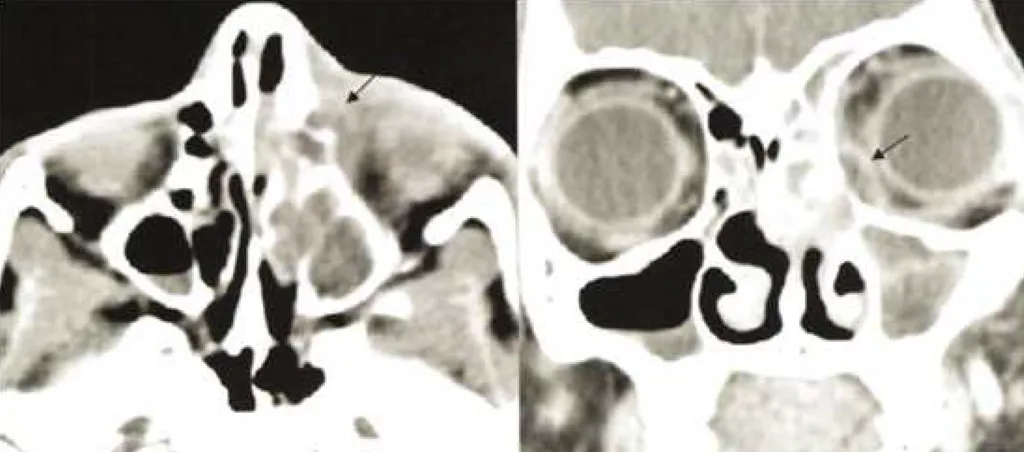

【113-1 醫學(六) 第23題】急性鼻竇炎(acute rhinosinusitis)之眼部併發症,依據 Chandler 分類,圖中的病例屬於那一類?

這張電腦斷層影像顯示眼眶內側有一個界線清楚的膿液堆積,將眼球和眼眶內容物往外推,這是典型的眼眶骨膜下膿瘍。